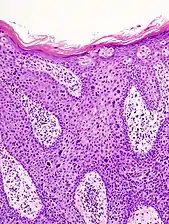

Histopathologically, the epidermis in cSCC in situ (Bowen's disease) will show hyperkeratosis and parakeratosis. There will also be marked acanthosis with elongation and thickening of the rete ridges. These changes will overly keratinocytic cells which are often highly atypical and may in fact have a more unusual appearance than invasive cSCC. The atypia spans the full thickness of the epidermis, with the keratinocytes demonstrating intense mitotic activity, pleomorphism, and greatly enlarged nuclei. They will also show a loss of maturity and polarity, giving the epidermis a disordered or "windblown" appearance.

Two types of multinucleated cells may be seen: the first will present as a multinucleated giant cell, and the second will appear as a dyskeratotic cell engulfed in the cytoplasm of a keratinocyte. Occasionally, cells of the upper epidermis will undergo vacuolization, demonstrating an abundant and strongly eosinophilic cytoplasm. There may be a mild to moderate lymphohistiocytic infiltrate detected in the upper dermis.[12]

In situ disease

Bowen's disease is essentially equivalent to and used interchangeably with cSCC in situ, when not having invaded through the basement membrane.[12] Depending on source, it is classified as precancerous[13] or cSCC in situ (technically cancerous but non-invasive).[46][47] In cSCC in situ (Bowen's disease), atypical squamous cells proliferate through the whole thickness of the epidermis.[12] The entire tumor is confined to the epidermis and does not invade into the dermis.[12] The cells are often highly atypical under the microscope, and may in fact look more unusual than the cells of some invasive squamous-cell carcinomas.[12]

cSCC in situ